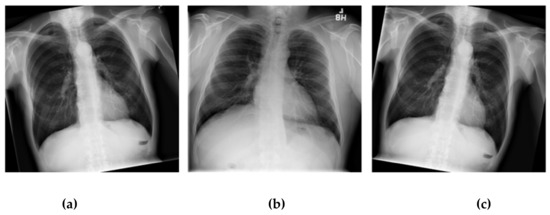

2.2. Dataset